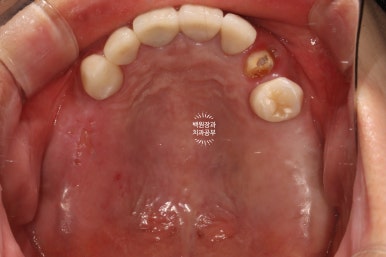

앞니 지르코니아 브릿지와 왼쪽 어금니 임플란트 완성!

앞니 지르코니아 브릿지와 왼쪽 어금니 임플란트가 완성되었습니다.

너무 색깔도 깔끔하게 잘 나오고... 만족스러운데요, 어디가 무엇인지 아시겠어요?

파란색으로 표시된 3개짜리가 앞니 지르코니아 브릿지이고,

보라색으로 표시된 2개짜리가 어금니 임플란트입니다.

진짜.. 내 치아라고 해도 잘 모르실거에요.

오래전에 하셨다는 아래 어금니 임플란트는 벌써 잇몸이 내려가 은색이 비쳐보이고 있네요... 여튼 이번에 새로한 치아들이 더 이쁘다는 말씀!

교합면에서 촬영한 것을 보면, 다수의 치야가 완성되어 드뎌 원래 치아가 있었던 상태로 돌아간 것을 보실 수 있어요.